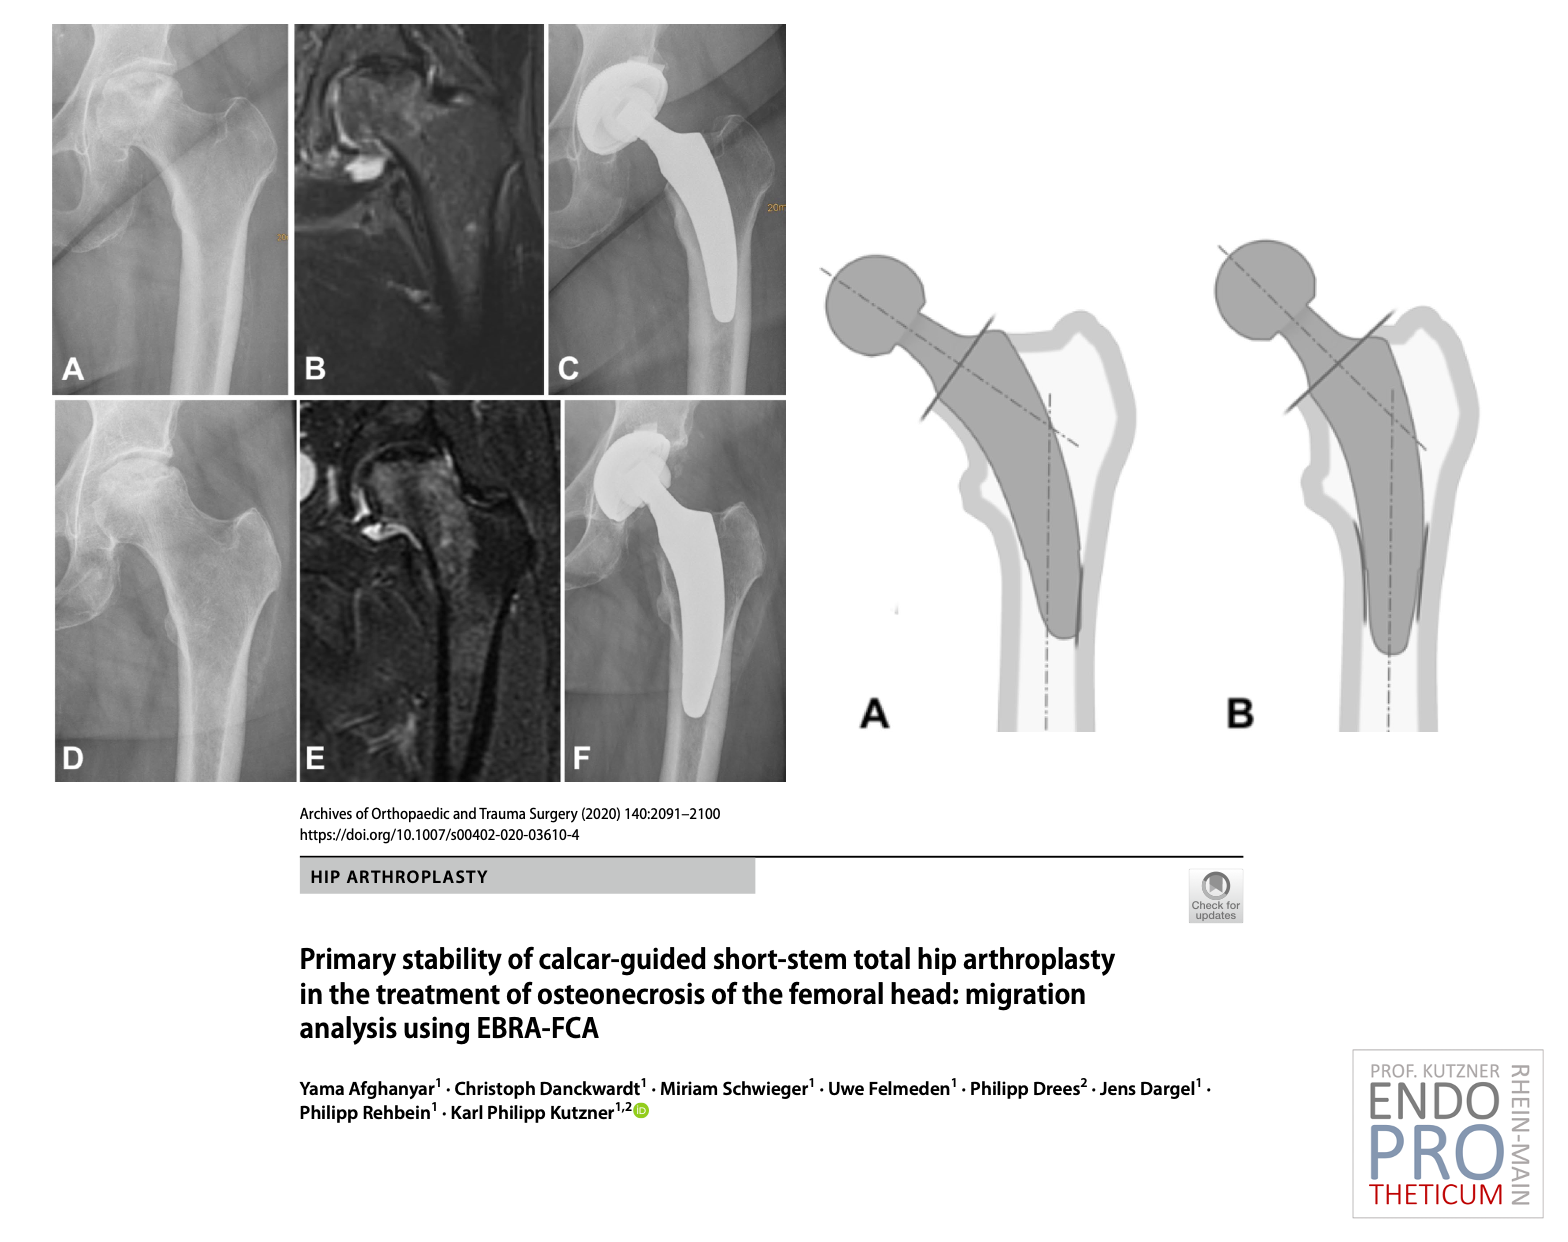

يهدف مفهوم السيقان القصيرة الحديثة الموجهة بالكلس في جراحة مفاصل الورك إلى إعادة البناء الدقيق لهندسة الورك التشريحية الفردية. يتم استخدام تقنية زرع لطيفة على العظام والأنسجة الرخوة بالتزامن مع التحميل الفسيولوجي في جزء عظم الفخذ بالقرب من المفصل من أجل الحفاظ على العظام على المدى الطويل.

تتلاءم الأعمدة القصيرة والمستديرة بشكل مثالي مع تقنية ALMIS ACCESS ذات التدخل الجراحي البسيط، وليس من الضروري أن تلحق الضرر بالعضلات. على عكس الأعمدة المستقيمة التقليدية، يتم إجراء عملية الزرع باستخدام تقنية "الزاوية المستديرة".